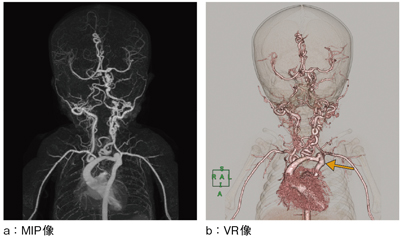

●症例1:大血管形成異常(図4)

他院の造影CTで頸動脈の異常血管を認めた生後間もない患児に,確定診断のため再度当院でCTAを施行した。自動サブトラクションにより,画像処理経験の浅い技師でも,頭部から胸部まで広範囲の複雑な異常血管を描出することができた。画像情報としては,大動脈弓部が低形成で蛇行し,狭窄が認められた(図4 b←)。また,右内頸動脈は起始部で閉塞し,頭蓋内は左内頸動脈,左椎骨動脈によって供血されていることを描出でき,治療方針が決定された。

図4 症例1:大血管形成異常